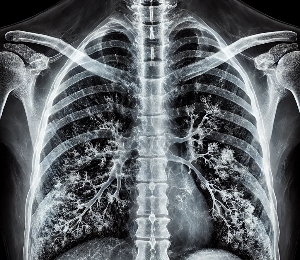

폐렴은 폐 조직에 염증이 생겨 호흡이 어려워지고, 심한 경우 폐 기능 저하로 이어질 수 있는 심각한 질환입니다.

병원에서의 엑스레이검사 및 정환한 약물치료를 한후에 완치후 체력 회복차 참고 하시기 바라며

폐는 한번 망가지면 회복이 어려운 장기 입니다.

전문 의사의 치료가 우선되어야 함을 명시 드립니다.